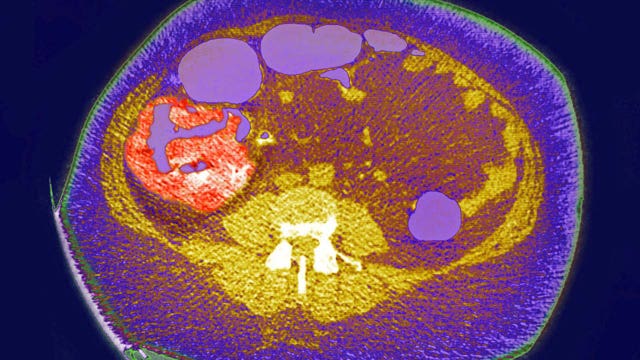

New genetic experiment was found to shrink woman's pancreatic cancer

Researchers culled T cells from the woman's blood and genetically engineered them to spot a mutant protein fueling her cancer.